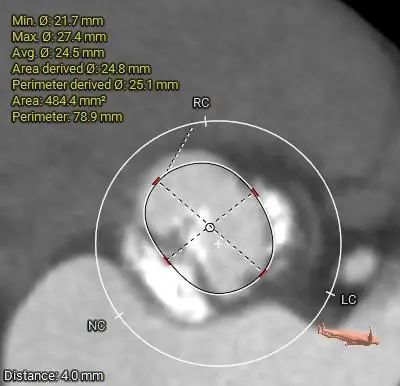

ANNULUS

SOV DIAMETER